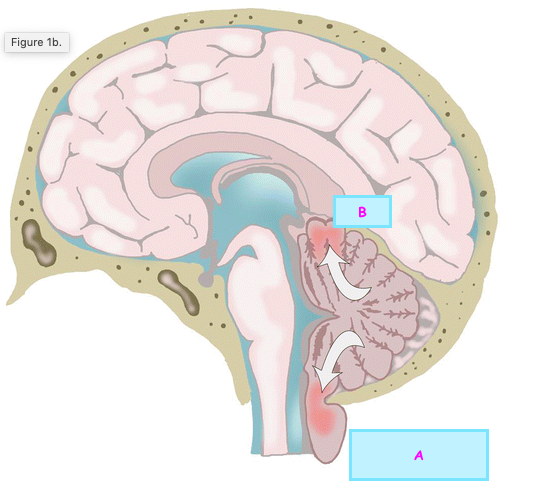

Which potential mechansim for DBS is depicted by the figure? 1- Inhibition hypothesis 2- Excitation hypothesis 3- Disruption hypothesis 4- Neuro-network modulation hypothesis

**3- Disruption hypothesis** DBS activates axon terminals in the stimulated nucleus, induces extensive release of neurotransmitters, such as GABA and glutamate (Glu), and dissociates inputs and outputs in the stimulated nucleus

260